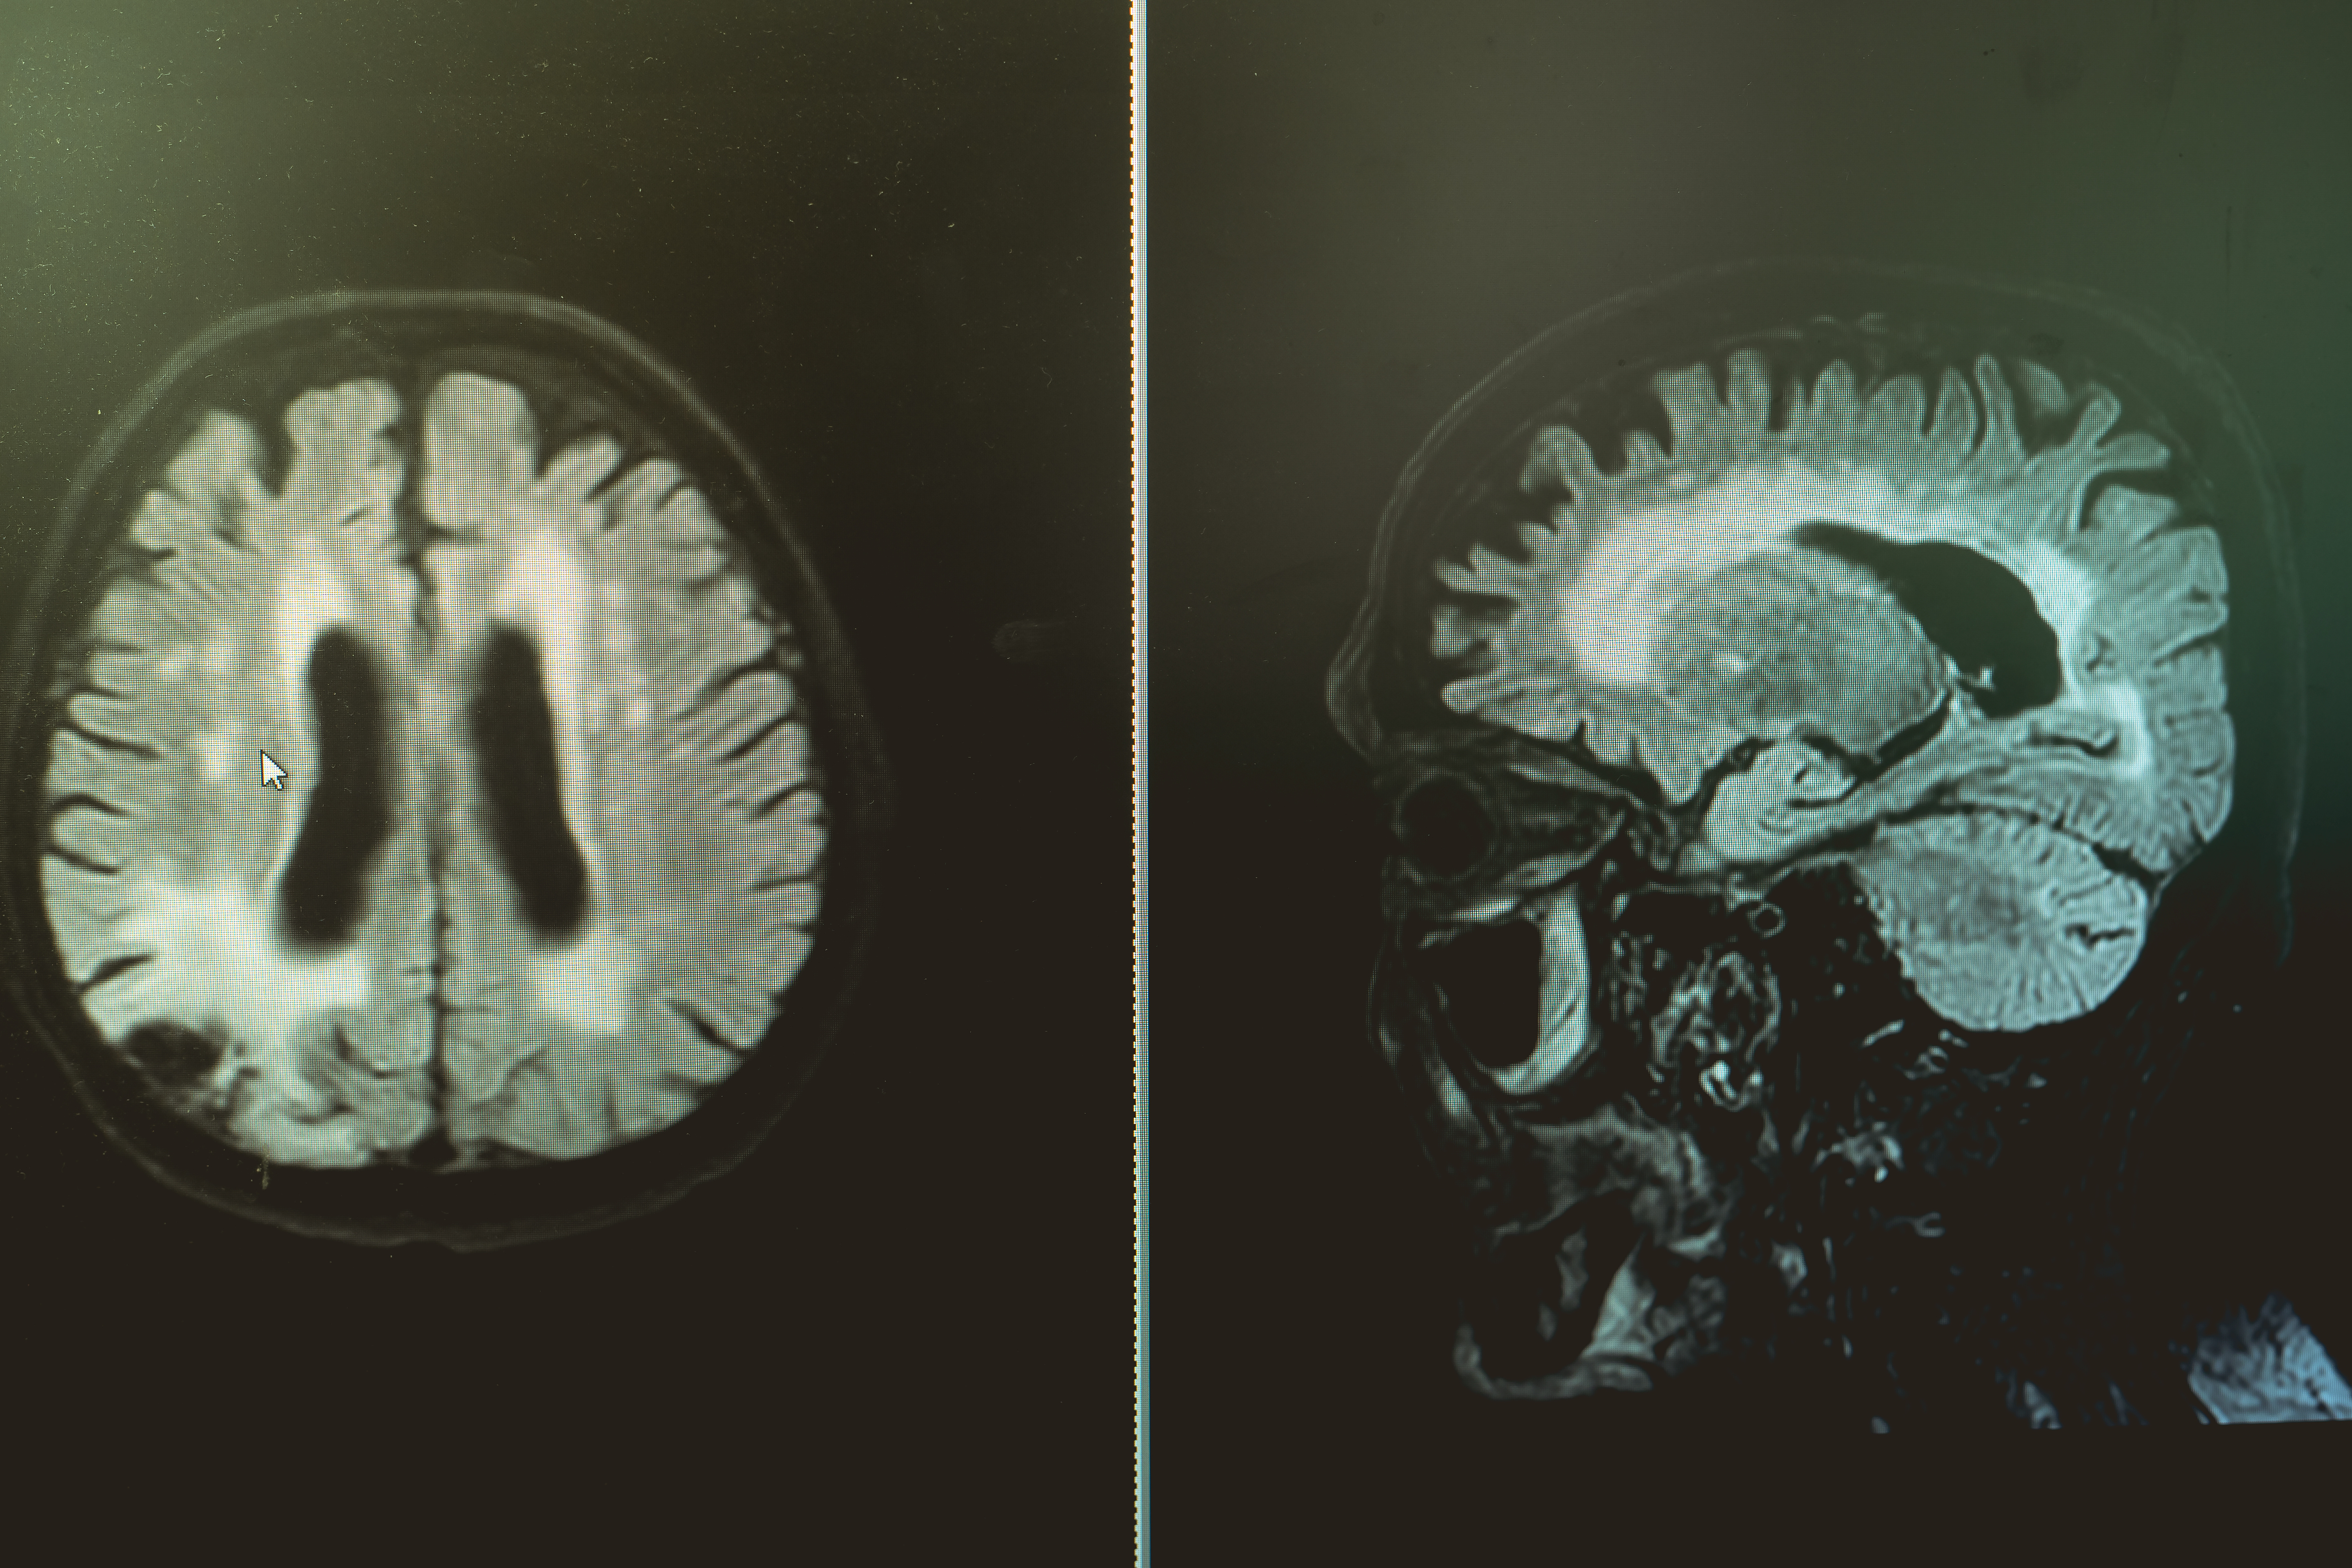

Emphasizing the proper diagnostic characterization of sidewall aneurysms, the authors of a new study found no significant differences in occlusion status or complications when they compared the approved use of intrasaccular flow disruption for bifurcation aneurysms to off-label treatment of sidewall aneurysms.